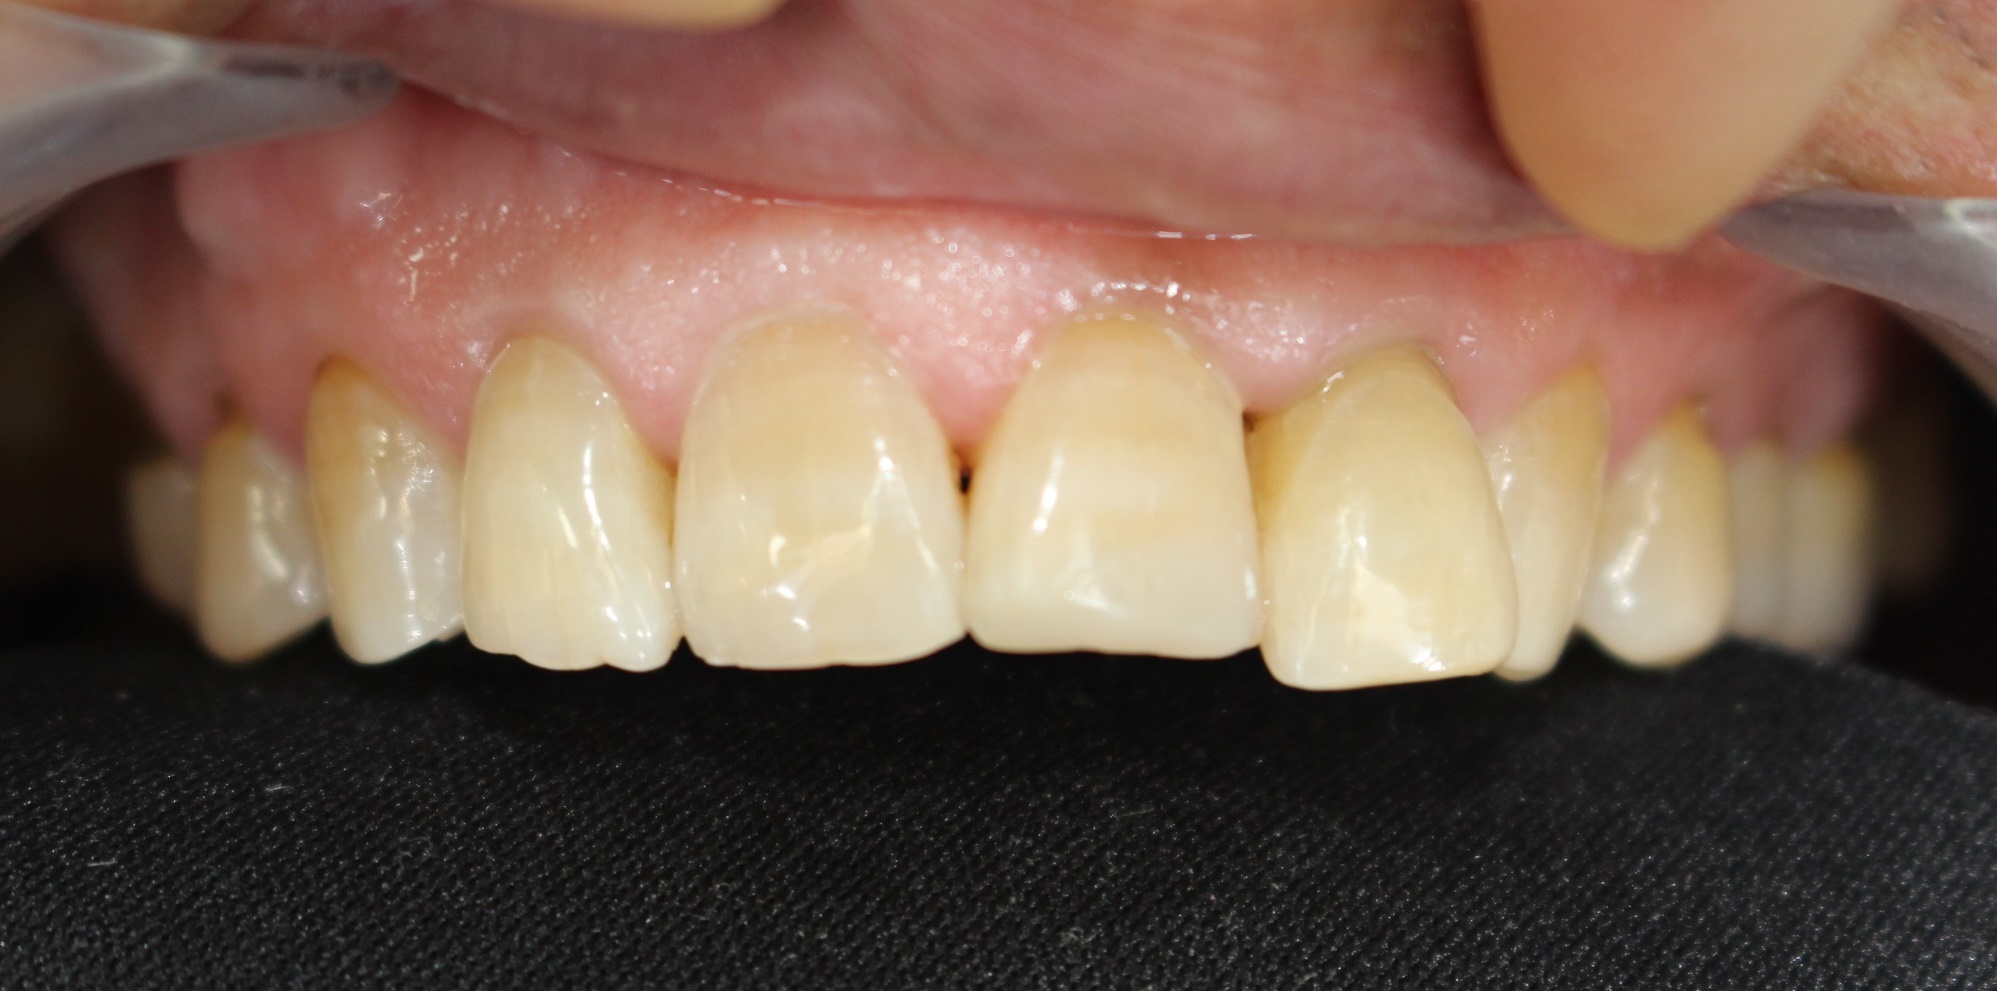

수술 전

수술 후

구치부 임플란트 식립사례

전후사진